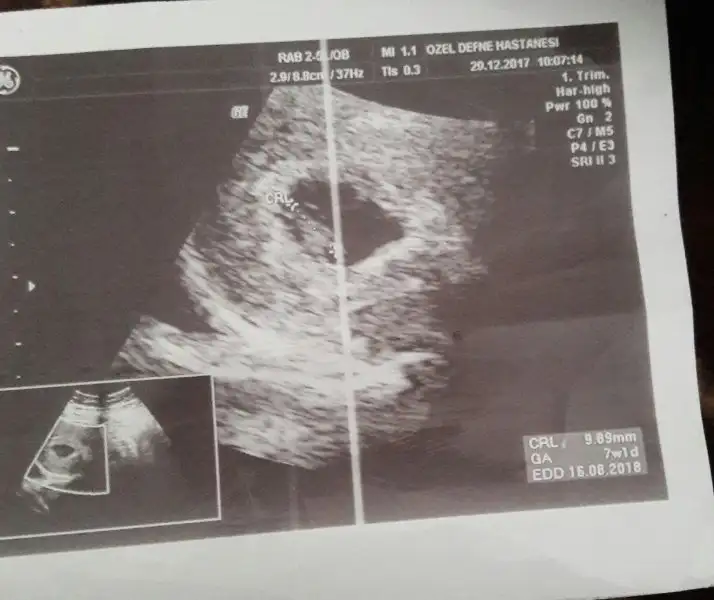

Bebegin Kesedeki Konumuna Göre Cinsiyet Tahmini

Benimki ne olabilir acaba çok merak ediyorum